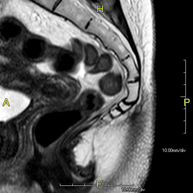

Prova diagnòstica no invasiva que consisteix en l'obtenció d'imatges d'alta definició anatòmica de la pelvis mitjançant l'ús d'un camp electromagnètic i ones de ràdio (amb un emissor i un receptor). No utilitza radiació ionitzant. Es realitza per a l'estudi de patologies d'úter, d'ovari, de trompes i de vagina, ja siguin d'origen tumoral, inflamatori o vascular. També permet valorar les estructures adjacents localitzades a la pelvis i la identificació de les seves alteracions. De vegades és necessari l'ús de contrast intravenós (Gadolini) per caracteritzar les lesions. - RM Pelvis masculina

Prova diagnòstica no invasiva que consisteix en l'obtenció d'imatges d'alta definició anatòmica de la pelvis masculina mitjançant l'ús d'un camp electromagnètic i ones de ràdio (amb un emissor i un receptor). No utilitza radiació ionitzant. No requereix preparació prèvia. En algunes ocasions necessita l'ús de contrast paramagnètic (Gadolini) per caracteritzar les lesions. Aquesta prova permet valorar òrgans com la bufeta urinària, la unió entre els urèters i la bufeta, la pròstata, les vesícules seminals, la uretra i els ossos de la pelvis, entre d'altres. - RM de Fetge